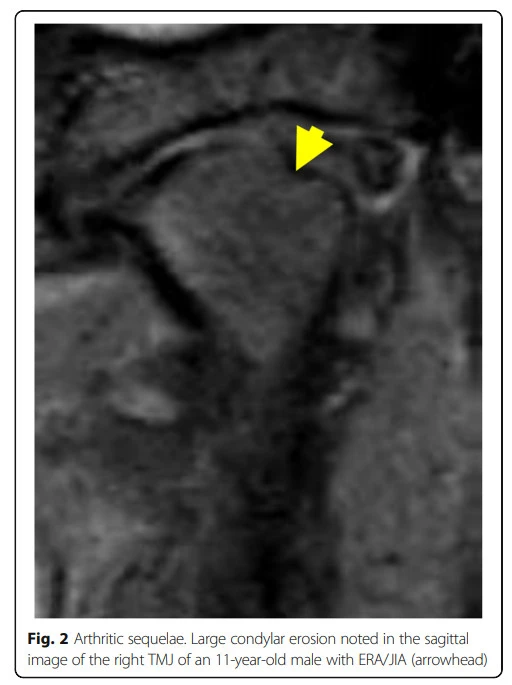

그림출처: Stoll, Matthew L., et al. "Temporomandibular joint arthritis in juvenile idiopathic arthritis, now what?." Pediatric Rheumatology 16.1 (2018): 32.

소아특발성관절염(Juvenile idiopathic arthritis, 앞으로 JIA라 약하겠습니다)이 턱관절에 침범하여 활동성인 경우에 나타나는 소견입니다. 왼쪽에 활막이 매우 비후해진 것을 볼 수가 있습니다.

아까 위의 사진에서 활막이 두꺼워지는 소견은 바로 윗그림의 synovial membrane이 두꺼워진 것이라 보시면 되는데 두께만 딱 봐도 염증이 심하다는 것을 알 수가 있습니다.